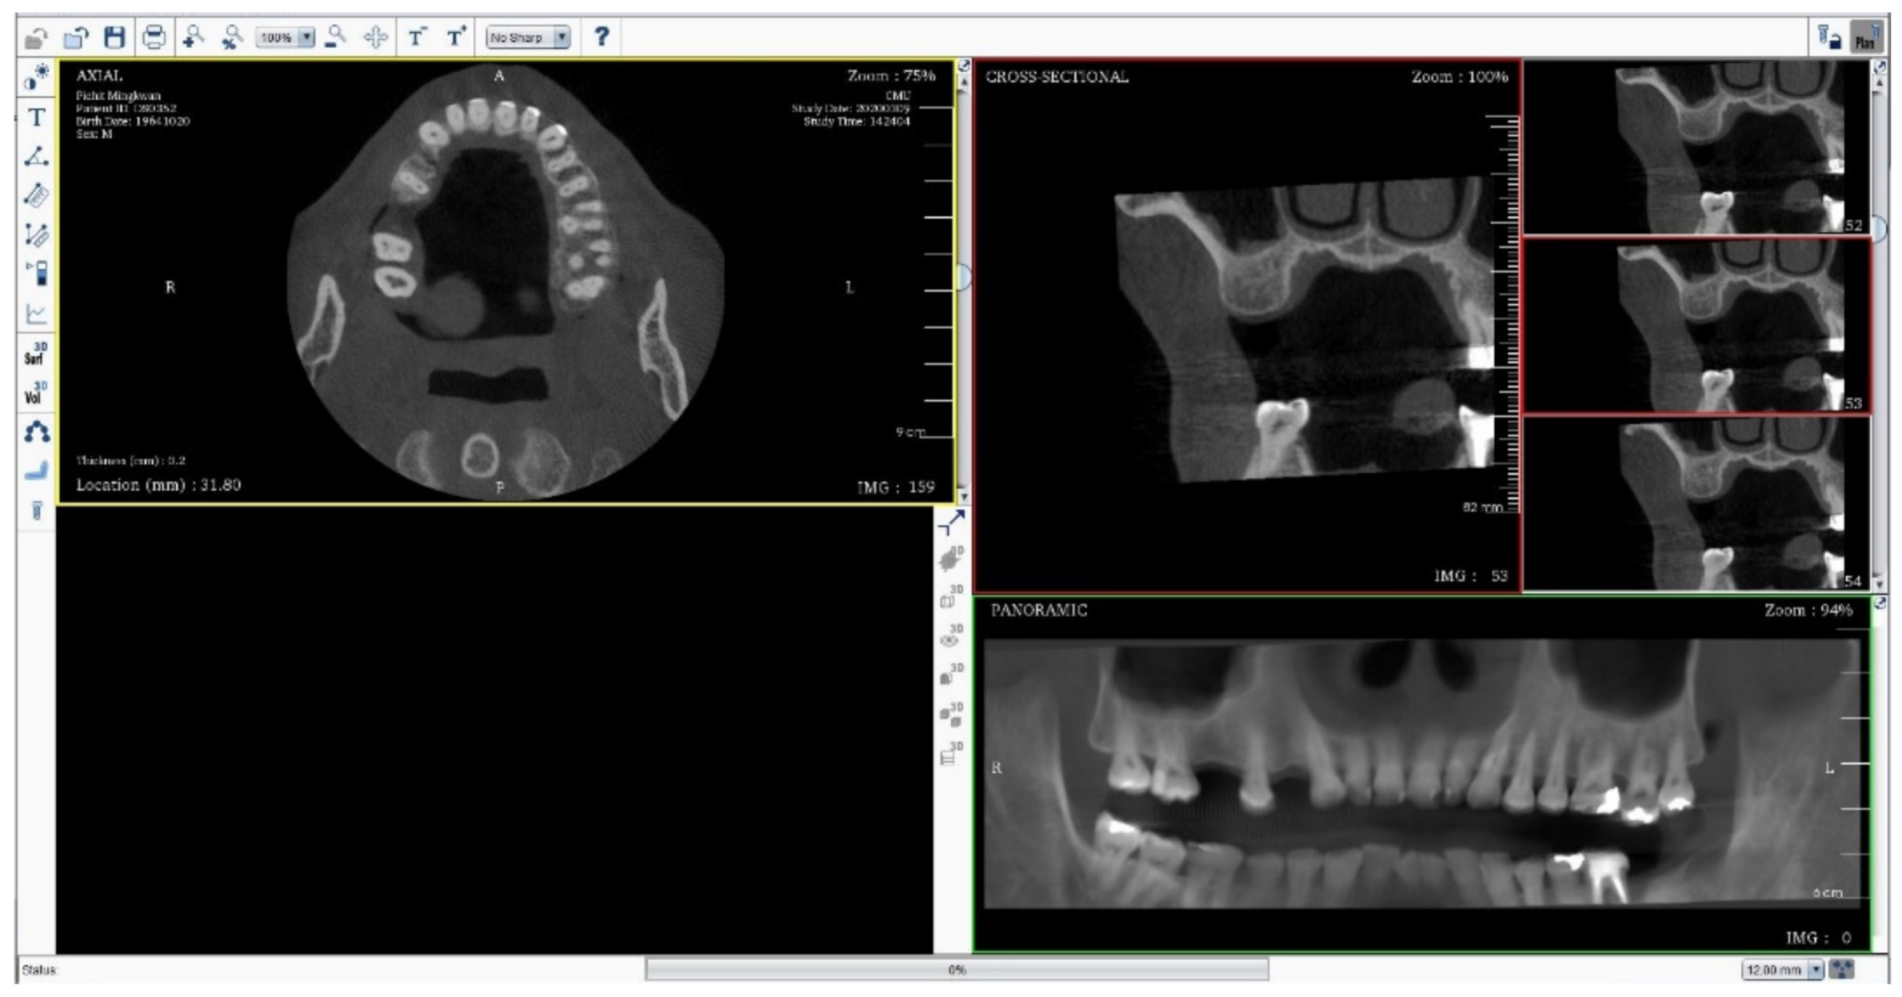

A total of 316 images were then anonymously captured to ensure that no private information was revealed. The full-screenshot images were taken from DTP software with the joint photographic expert group (JPEG) format at 1920 × 1080 pixels with 24-bit depth (Figure 1). Three hundred images were used for model training, which were randomly sorted from 1–300 to create six data sets, including 1–50, 1–100, 1–150, 1–200, 1–250, and 1–300. These six data sets were called the training set. The remaining 16 images were selected for accuracy testing to assess the performance of the developed model; this set of 16 images was called the testing set.

Figure 1.

The full screen image capture of DentiPlan Pro version 3.7.